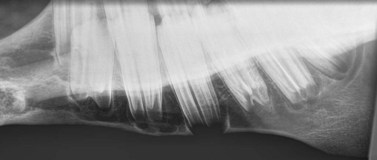

image

Fig. 13.29 Lateral oblique radiograph of the hemimandible of a normal 3-year-old horse. Note the wide, rounded, radiolucent periapical regions of the 07 and 08 which are termed ‘eruption cysts’. The ventral cortex of the mandible beneath the 08 is convex and extremely thin and appears radiolucent.

The dental buds of the permanent cheek teeth in the young horse are large, rounded, radiolucent structures, with a striated, vertical radiodense pattern, which is due to partially calcified enamel folds (Fig. 13.26). As a dental bud develops into a cheek tooth, its apical aspect appears as a round, radiolucent area with a very wide periodontal space, which is termed an eruption cyst. The lamina dura is often not visible around the apices of developing teeth. The permanent equine CT erupt between 1 and 4 years of age (see Ch. 5). Between 2 and 4 years of age (Fig. 13.29), the reserve crown is very long, and many of the cheek teeth still have large eruption cysts. At this age, the ventral border of the mandible becomes convex in some breeds (‘3- and 4-year-old bumps’) to accommodate these large dental structures, and the ventral mandibular cortex beneath the eruption cysts is very thin or even appears fully eroded. This convex appearance is lost as the horse ages due to continued eruption of the reserve crown, maturation of the cheek teeth apices, and remodelling of the mandibular cortex.

As the horse ages and the cheek teeth erupt, the true roots (i.e., enamel-free areas) develop, and the apices change from being rounded to developing a number of pointed structures, i.e., true roots (Fig. 13.30). Bearing in mind that the equine cheek teeth erupt at different ages, it is normal for young horses to have adjacent cheek teeth with very radiographically variable apical areas (Fig. 13.29). For example, major differences are present between the apices of the 08s (3rd cheek teeth) and 09s (4th cheek teeth) in a 4-year-old horse, because the 09 is 3 years older than the 08. Consequently, caution must be exercised when comparing the radiographic appearances of adjacent cheek teeth apices in young horses.